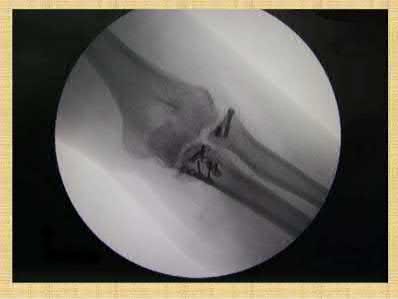

The clinical presentation is consistent with a coronoid tip fracture. This fracture pattern is associated with a radial head fracture and posterolateral ulnohumeral dislocation - together making up the terrible triad injury.

A terrible triad injury is the result of a valgus and supination injury and involves posterolateral elbow dislocation or lateral collateral ligament injury, radial head fracture, and fracture of the coronoid process. The elbow may dislocate postero-laterally with the anterior bundle of the MCL intact, but if the MCL is injured it is typically the last structure to fail. The coronoid fracture is typically a small fragment isolated to the tip. This is a result of a posteriorly directed force driving the coronoid into the trochlea prior to posterior elbow dislocation. CT scan is a useful modality when small or comminuted fragments are difficult to visualize on plain radiographs.

Figures A through D show consecutive 2.00 mm sagittal CT reformats demonstrating a small coronoid fracture fragment which was addressed with suture fixation.